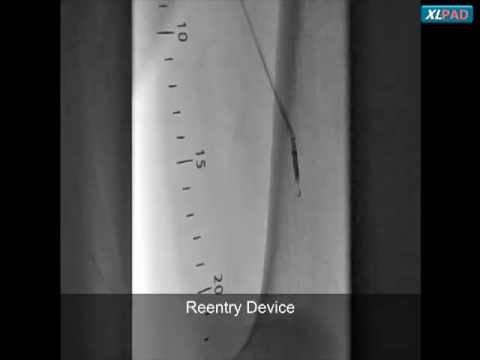

TruePath to Cross Left SFA CTO with Subintimal Re-Entry